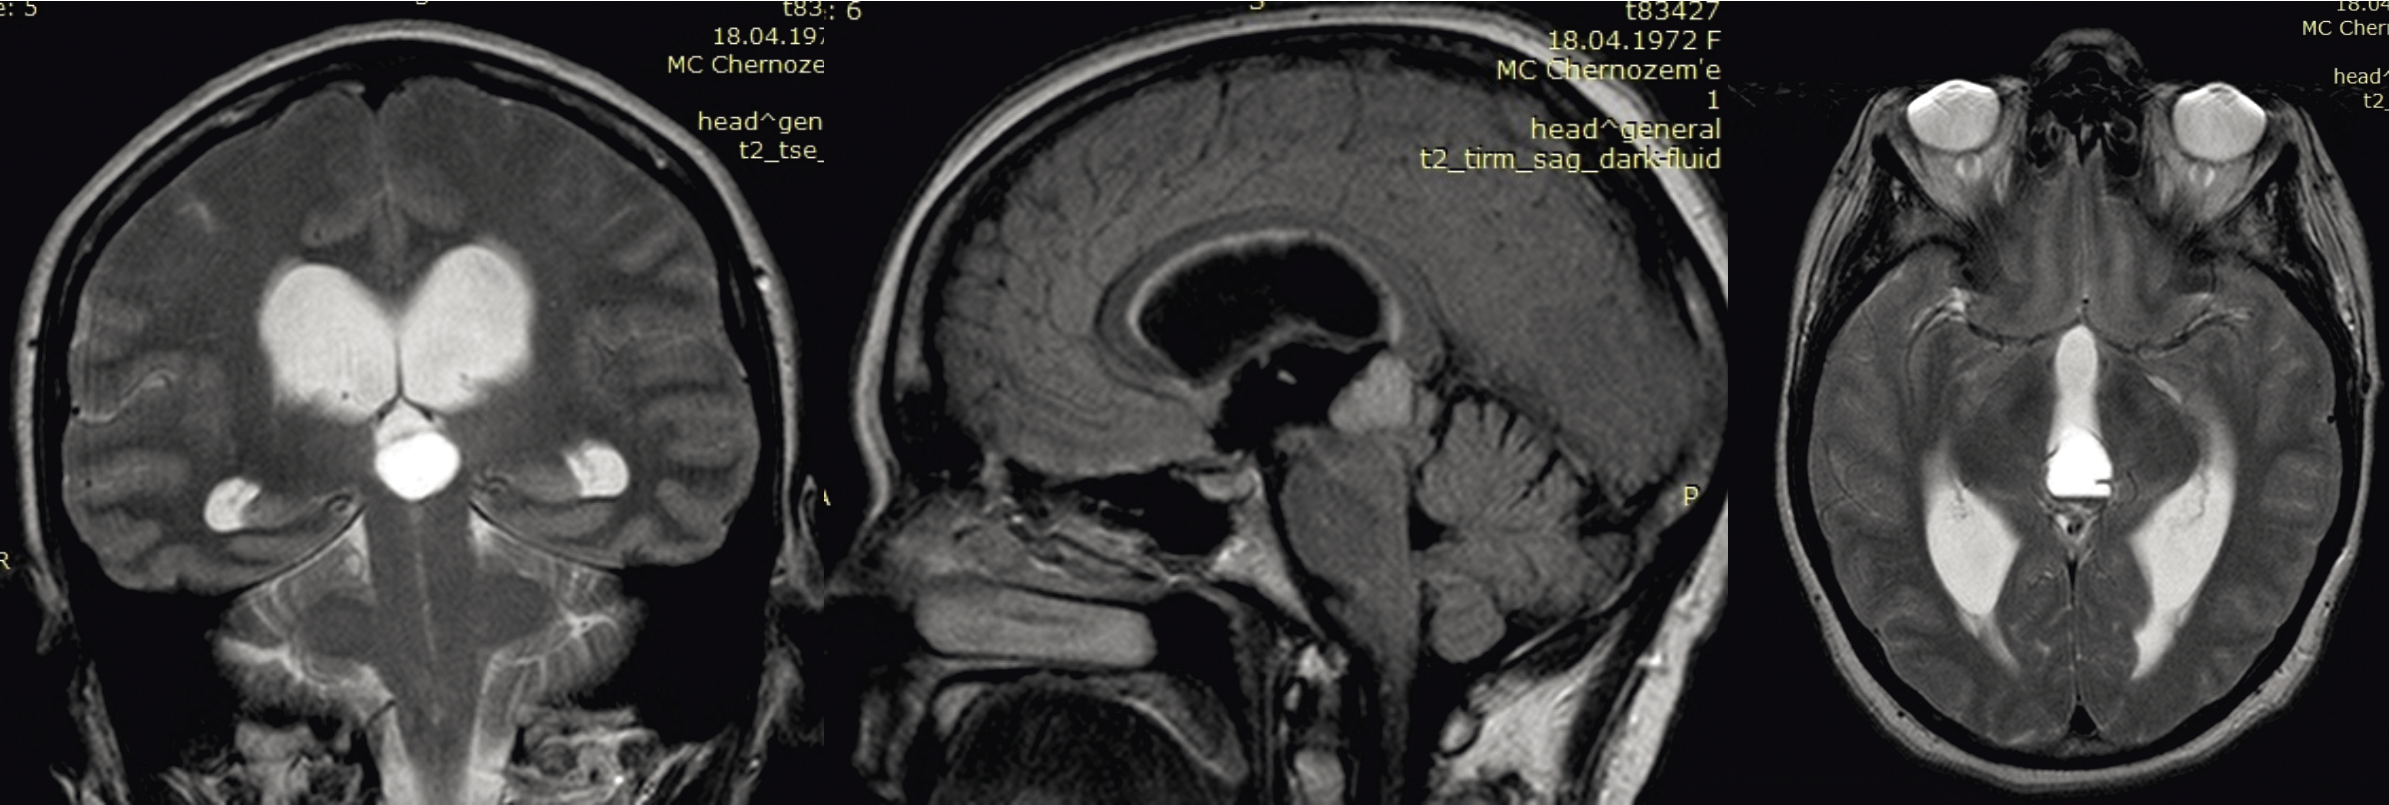

Данные МРТ больной до операции: в пинеальной области по средней линии визуализируется солидное объемное новообразование эпифиза с распространением на задние отделы III желудочка с дислокацией четверохолмия (рис. 1).

Рис. 1. МРТ головного мозга с внутривенным контрастированием у больной с опухолью эпифиза